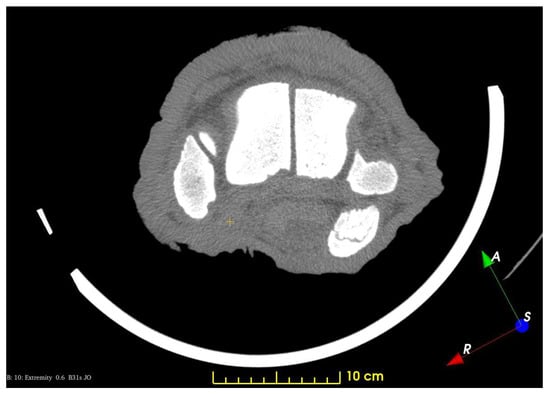

3. Results and Discussion

3.1. The Skeleton of the Forefoot

3.2. Results of the Vessel Reconstructions